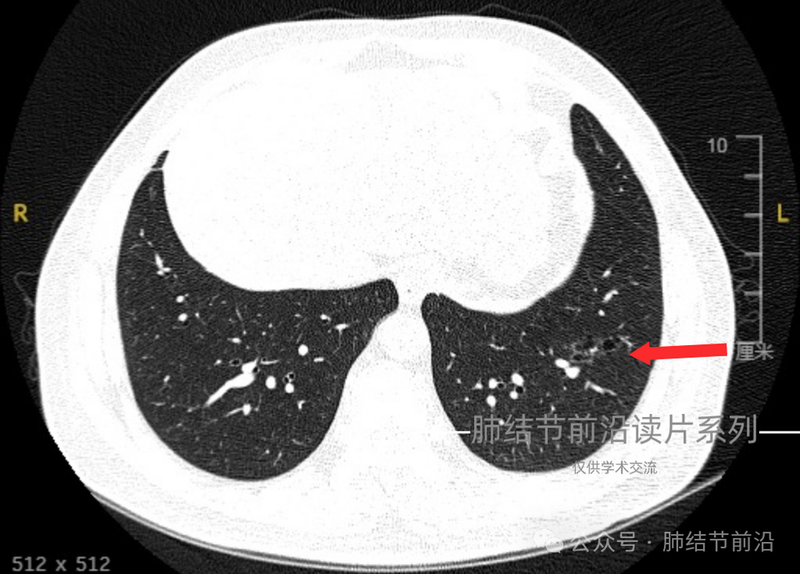

空泡型肺癌的形态有时不典型,重点观察空泡周围的磨玻璃影,基本可以确认为肿瘤性。

空泡+磨玻璃影样要高度怀疑腺癌,典者很容易诊断。但本例形态有些不典型,磨玻璃影不规则且狭长,容易误判为炎症。但是空泡为多个融合,显然不能用炎症解释。多读片,可以依靠这个空泡周边磨玻璃影不吸收这个典型症像,把握尽早确诊腺癌,以免延误。